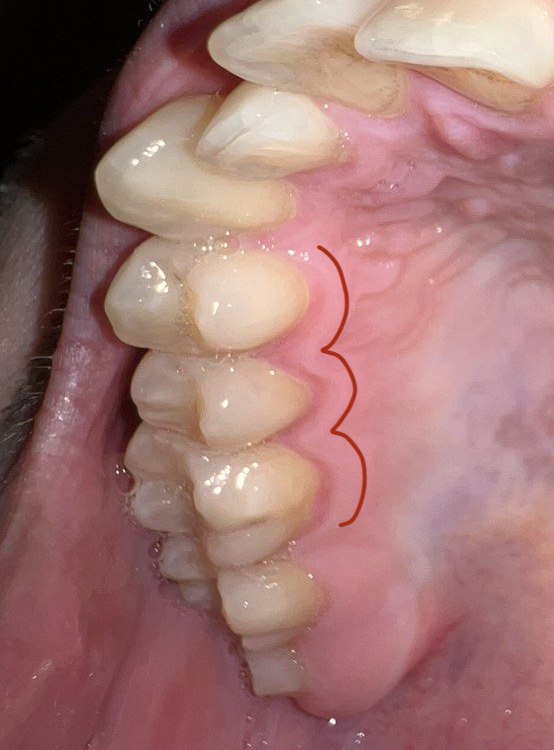

Аноним 11/09/25 Чтв 21:08:21 1639599 115

>>1639449

Такая же хуйня была, пока на проф.чистку не сходил, лул.

Аноним 11/09/25 Чтв 21:15:31 1639601 116

>>1631979 (OP)

Есть все же какой-то одобренный Двачом гайд, что можно жрать с брекетами, а что нельзя?

Поставили только сегодня на верхнюю челюсть для начала, пока сижу на йогуртах, но ясен хуй, дело так далеко не пойдет, а в интернетах одни пишут, что лучше запитываться от аккумулятора, а другие, что основа здорового завтрака для брекетоносца это куски бетона со стальной стружкой. Сама врач сказала, что липкого-твердого нельзя, И ХЛЕБ ХЛЕБ БЛЯТЬ НЕ ЕШЬ, НЕ ЕШЬ СУКА ХЛЕБ

Аноним 11/09/25 Чтв 22:59:56 1639614 117

>>1632648

А какие симптомы пульпита?

Аноним 11/09/25 Чтв 23:55:50 1639622 118

Аноним 12/09/25 Птн 05:12:51 1639626 119

>>1639599

Ты про камень у основания зубов или темно-розовую обводку, скажем, на десне как у меня где десна в зубы переходят?